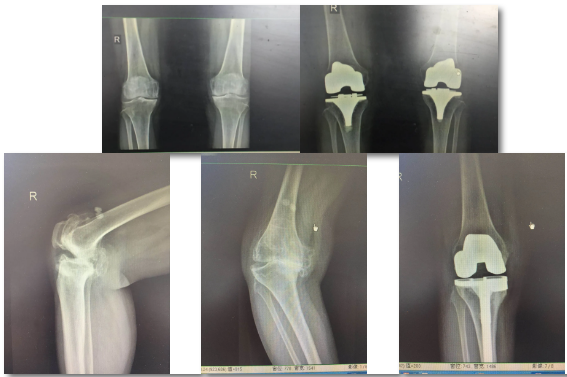

保膝治療

膝骨關節(jié)炎患者是臨床常見的老年關節(jié)疾病,骨二科根據患者病情綜合評估考量,對較年輕患者采用膝關節(jié)鏡清理加腓骨截骨術,對脛骨近端內翻畸形且外側關節(jié)間隙良好的患者采用膝關節(jié)鏡清理加脛骨近端高位截骨術或單髁置換術,恢復患者膝關節(jié)正常力線,減緩或避免最終的膝關節(jié)置換治療。

腓骨截骨術

單踝置換

膝關節(jié)置換

嚴重膝關節(jié)疾病導致全膝破壞的終極治療是膝關節(jié)置換,骨二科采用內軸膝系統,能更好的模擬膝關節(jié)的正?;顒?,完美恢復膝關節(jié)的功能,達到Forget knee的效果。